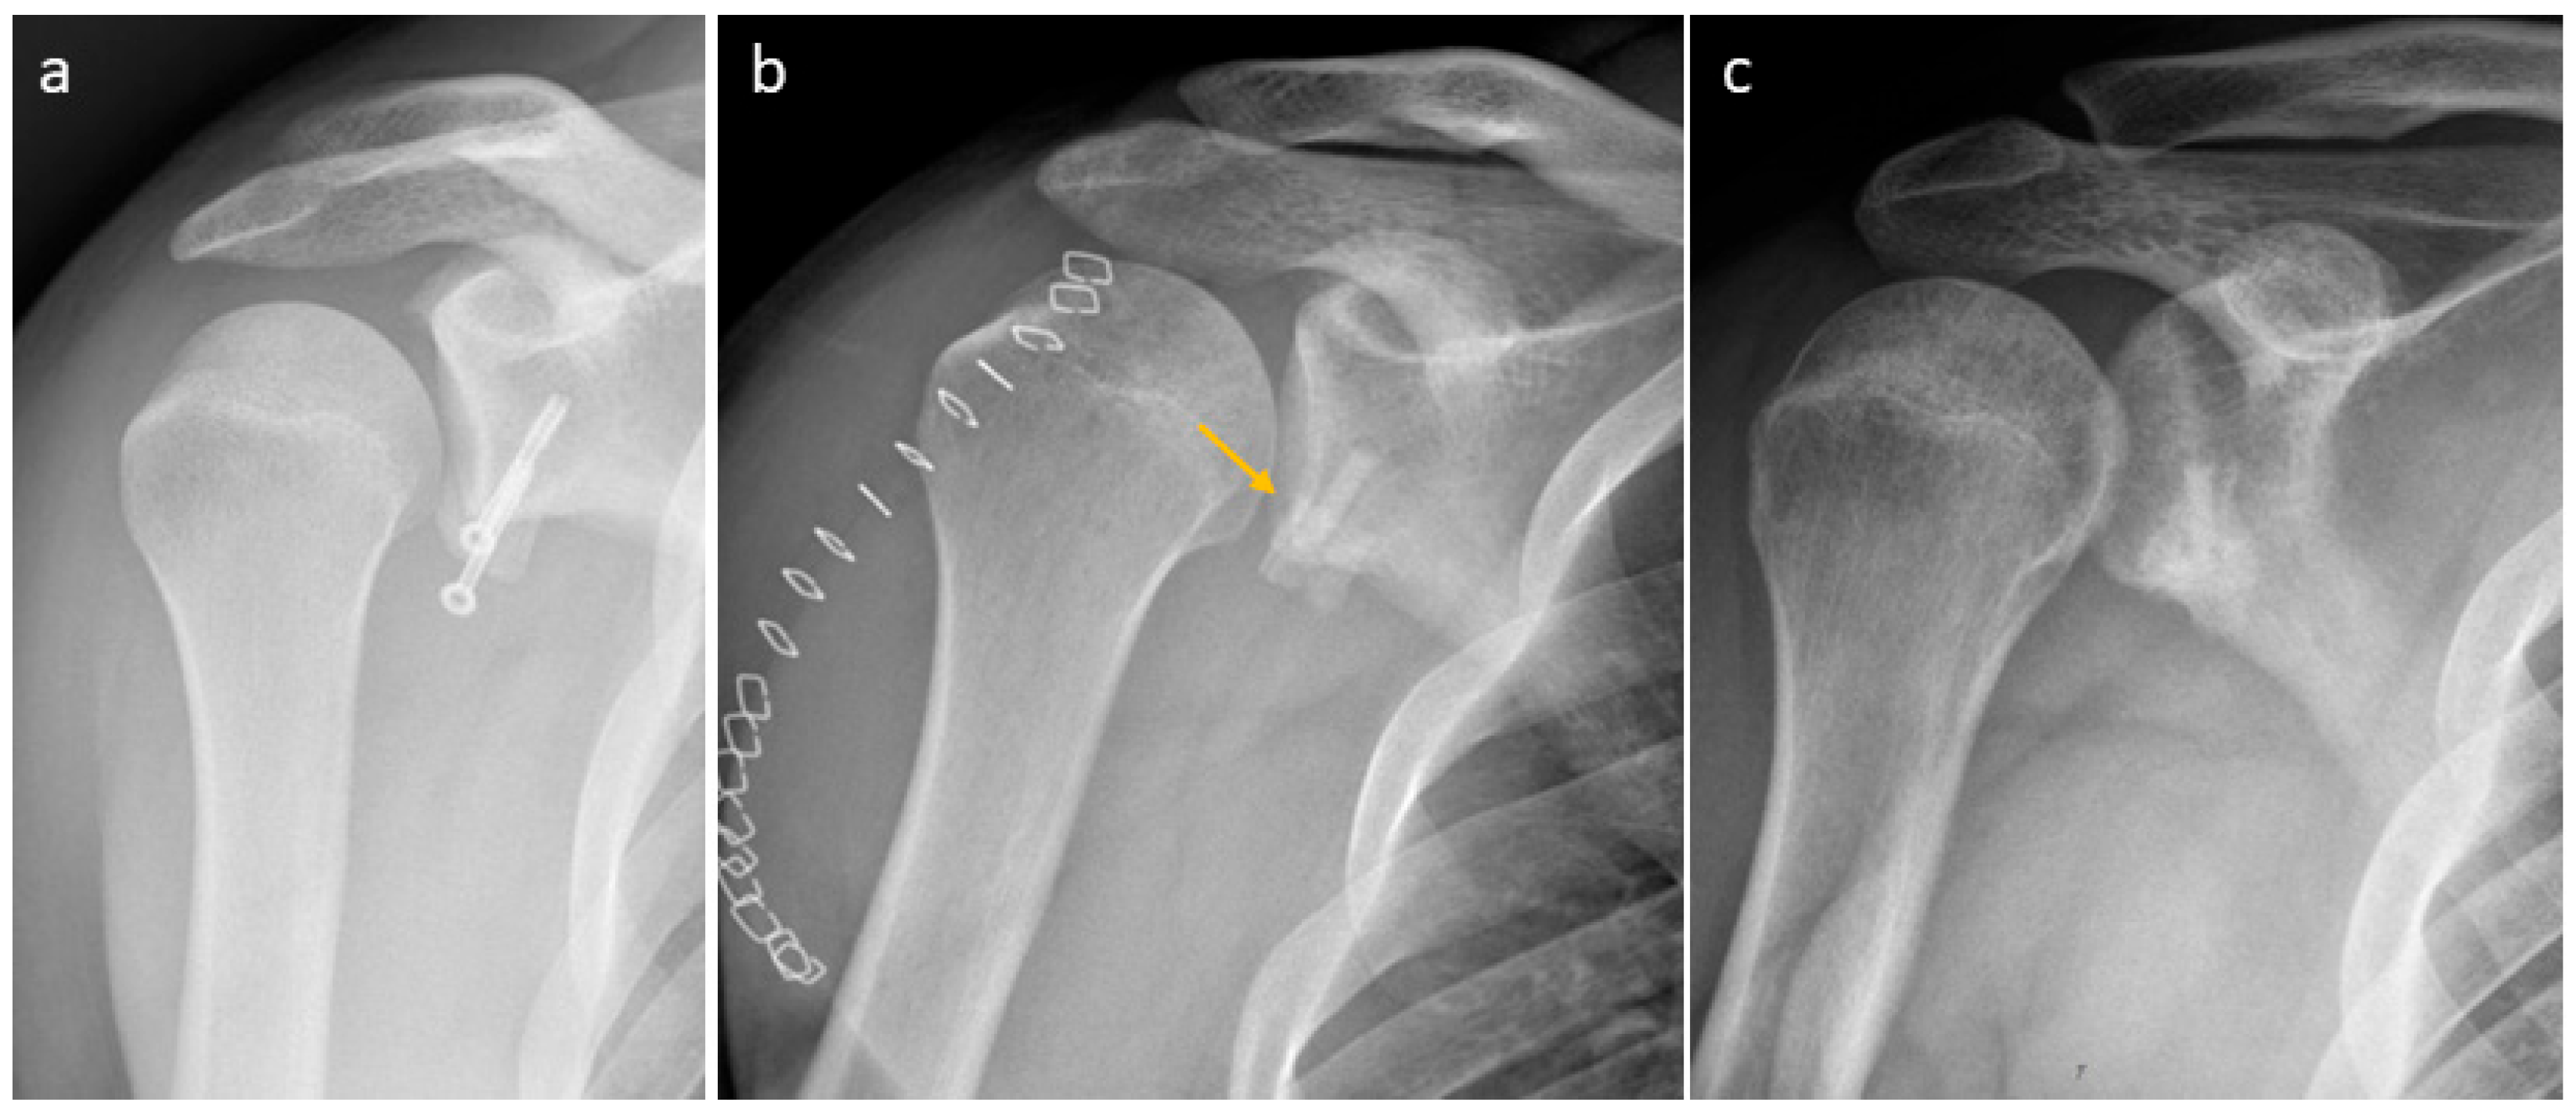

3.4. Selected Case Descriptions